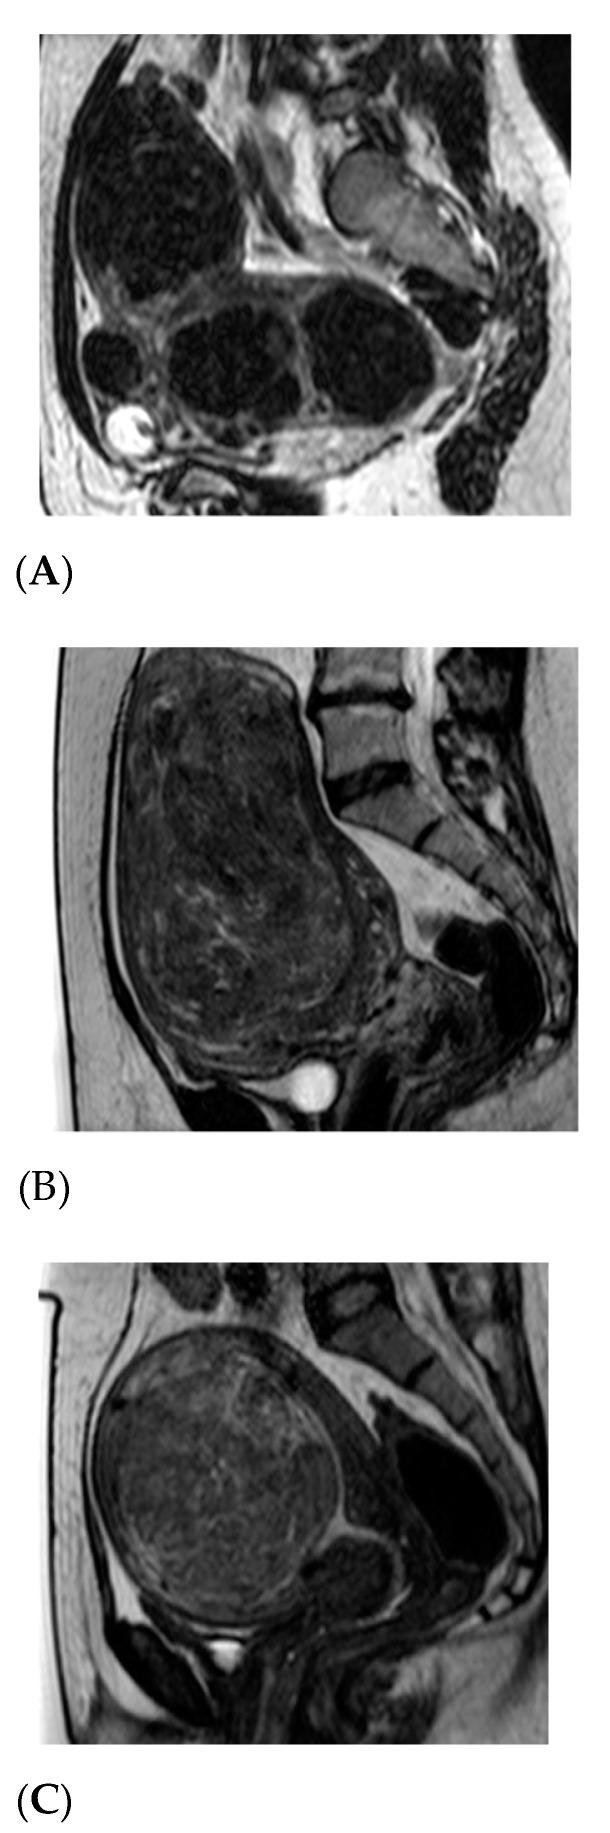

磁共振引导高强度聚焦超声消融子宫肌瘤——利用动态对比增强磁共振成像进行疗效评估及宫缩剂给药的潜在作用

Magnetic Resonance-Guided High-Intensity Focused Ultrasound Ablation of Uterine Fibroids-Efficiency Assessment with the Use of Dynamic Contrast-Enhanced Magnetic Resonance Imaging and the Potential Role of the Administration of Uterotonic Drugs.

The assessment of the usefulness of dynamic contrast-enhanced magnetic resonance imaging (DCE-MRI) when qualifying patients with uterine fibroids (UFs) for magnetic resonance-guided high-intensity ultrasound (MR-HIFU).

MATERIAL AND METHODS

This retrospective, single center study included 283 women who underwent DCE-MRI and were treated with MR-HIFU. The patients were divided according to non-perfused volume (NPV) as well as by the type of curve for patients with a washout curve in the DCE-MRI study and patients without a washout curve. The studied women were assessed in three groups according to the type of uterotonics administered. Group A (57 patients) received one dose of misoprostol/diclofenac transvaginally and group B (71 patients) received oxytocin intravenously prior to the MR-HIFU procedure. The remaining 155 women (group C) were treated with the traditional non-drug enhanced MR-HIFU procedure.

RESULTS

The average NPV value was higher in no washout group, and depended on the uterotonics used.

CONCLUSIONS

We demonstrated a correlation between dynamic contrast enhancement curve types and the therapeutic efficacy of MR-HIFU. Our results suggest that DCE-MRI has the potential to assess treatment outcomes among patients with UFs, and patients with UFs that present with a washout curve may benefit from the use of uterotonic drugs. More studies are required to draw final conclusions.